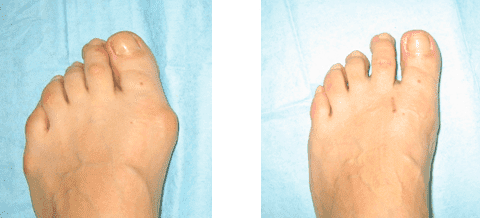

Ecco come sono le mie gambe un anno dopo aver usato Artrosteel

Dopo una settimana, il tumore ha iniziato a ridursi, e dopo due settimane era completamente scomparso. Il pollice è tornato gradualmente al suo posto e alla fine del corso era completamente stabilizzato! Ragazze, non è un miracolo?